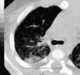

Slowly-resolving pneumonia

Pneumonia is an inflammatory condition of the lung primarily affecting the small air sacs known as alveoli. Symptoms typically include some combination of productive or dry cough, chest pain, fever and difficulty breathing. [Source: Wikipedia ]